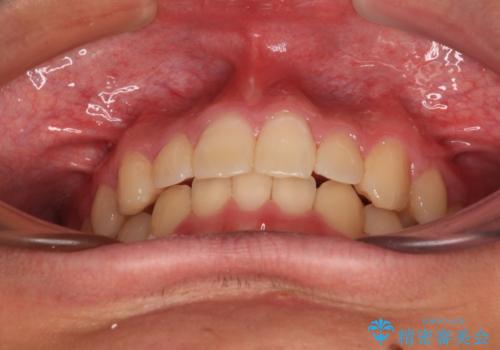

傾斜しいている大臼歯を立ち上げながら、下顎歯列を上顎に対して前方位となるように工夫し、デコボコを解消した上でディープバイトも改善することができました。